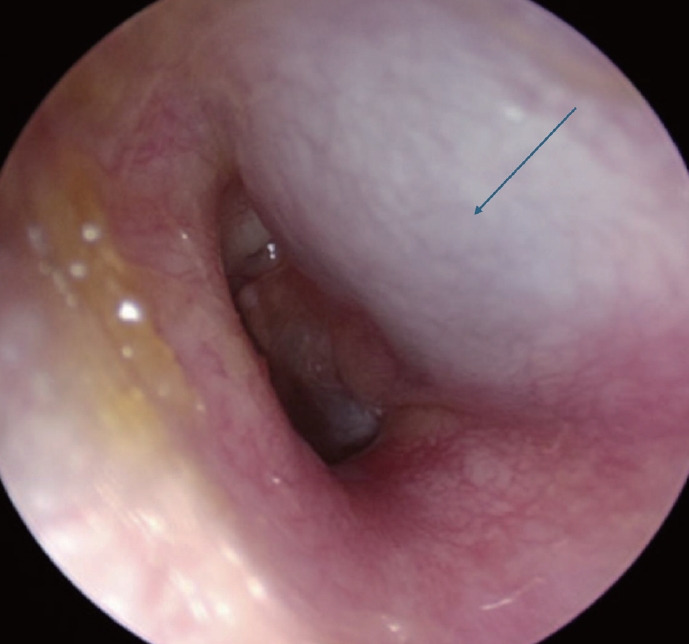

A 19-year-old male patient with a history of congenital left oval window defect has had recurrent admissions to a children's hospital for bacterial meningitis since the age of 7. Investigations revealed a left-sided type 1 incomplete partition deformity of the left ear with a congenital oval window defect, leading to communication between the cranium and the middle ear. The patient underwent a left canal wall down mastoidectomy and oval window defect repair, remaining well for 3 years. He experienced two more episodes of bacterial meningitis as he got older, prompting repeated exploratory tympanotomy and repair of the cerebrospinal fluid (CSF) leak after each episode. Recently, he was referred again for recurrent meningitis. Investigations showed a recurrent oval window defect. After undergoing left external ear canal transection, mastoid and middle ear obliteration, and left Eustachian tube obliteration, he remained well without further leaks or meningitis. Congenital oval window defect is rare and may present with recurrent bacterial meningitis secondary to spontaneous CSF leak via the oval window. Radiology plays a crucial role in identifying the source of the CSF leak, facilitating more precise preoperative counseling and surgical intervention.

{"title":"Recurrent Meningitis Following Previous Repair of Congenital Oval Window Defect.","authors":"Wan Qi Lim, Cherie Xinyi Seah, Kevin Chi Chuen Choy, Seng Beng Yeo, Jane Peiwen Lim","doi":"10.7874/jao.2024.00325","DOIUrl":null,"url":null,"abstract":"<p><p>A 19-year-old male patient with a history of congenital left oval window defect has had recurrent admissions to a children's hospital for bacterial meningitis since the age of 7. Investigations revealed a left-sided type 1 incomplete partition deformity of the left ear with a congenital oval window defect, leading to communication between the cranium and the middle ear. The patient underwent a left canal wall down mastoidectomy and oval window defect repair, remaining well for 3 years. He experienced two more episodes of bacterial meningitis as he got older, prompting repeated exploratory tympanotomy and repair of the cerebrospinal fluid (CSF) leak after each episode. Recently, he was referred again for recurrent meningitis. Investigations showed a recurrent oval window defect. After undergoing left external ear canal transection, mastoid and middle ear obliteration, and left Eustachian tube obliteration, he remained well without further leaks or meningitis. Congenital oval window defect is rare and may present with recurrent bacterial meningitis secondary to spontaneous CSF leak via the oval window. Radiology plays a crucial role in identifying the source of the CSF leak, facilitating more precise preoperative counseling and surgical intervention.</p>","PeriodicalId":44886,"journal":{"name":"Journal of Audiology and Otology","volume":"29 1","pages":"75-78"},"PeriodicalIF":1.4000,"publicationDate":"2025-01-01","publicationTypes":"Journal Article","fieldsOfStudy":null,"isOpenAccess":false,"openAccessPdf":"https://www.ncbi.nlm.nih.gov/pmc/articles/PMC11824527/pdf/","citationCount":"0","resultStr":null,"platform":"Semanticscholar","paperid":null,"PeriodicalName":"Journal of Audiology and Otology","FirstCategoryId":"1085","ListUrlMain":"https://doi.org/10.7874/jao.2024.00325","RegionNum":0,"RegionCategory":null,"ArticlePicture":[],"TitleCN":null,"AbstractTextCN":null,"PMCID":null,"EPubDate":"2025/1/20 0:00:00","PubModel":"Epub","JCR":"Q3","JCRName":"OTORHINOLARYNGOLOGY","Score":null,"Total":0}